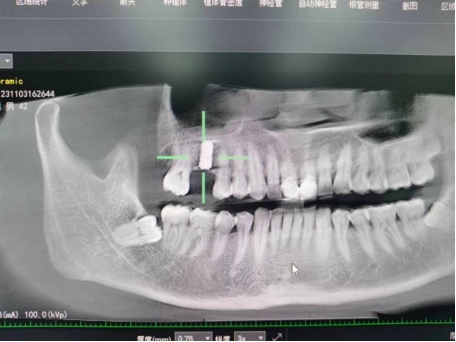

武先生术前检查图

据了解,53岁的武先生,因右上后牙缺失多年,缺失的牙齿给他造成了不小的烦恼,影响到了正常咀嚼功能。在了解到公司口腔科能开展种植牙手术以后,武先生前来咨询,经过仔细全面的口腔检查和CT检查、检验等检查,武先生符合种植牙条件,决定实施右上后牙区种植牙的修复方案。本次手术由陈河林博士主刀,黄魁副主任做助手,在口腔中心成功完成该院首例种植牙手术,手术历时约30分钟,术中微创操作,患者全程无痛,术后无不良反应,整个诊疗过程舒适、安全、精准,经术后CT检查种植体位置精确。